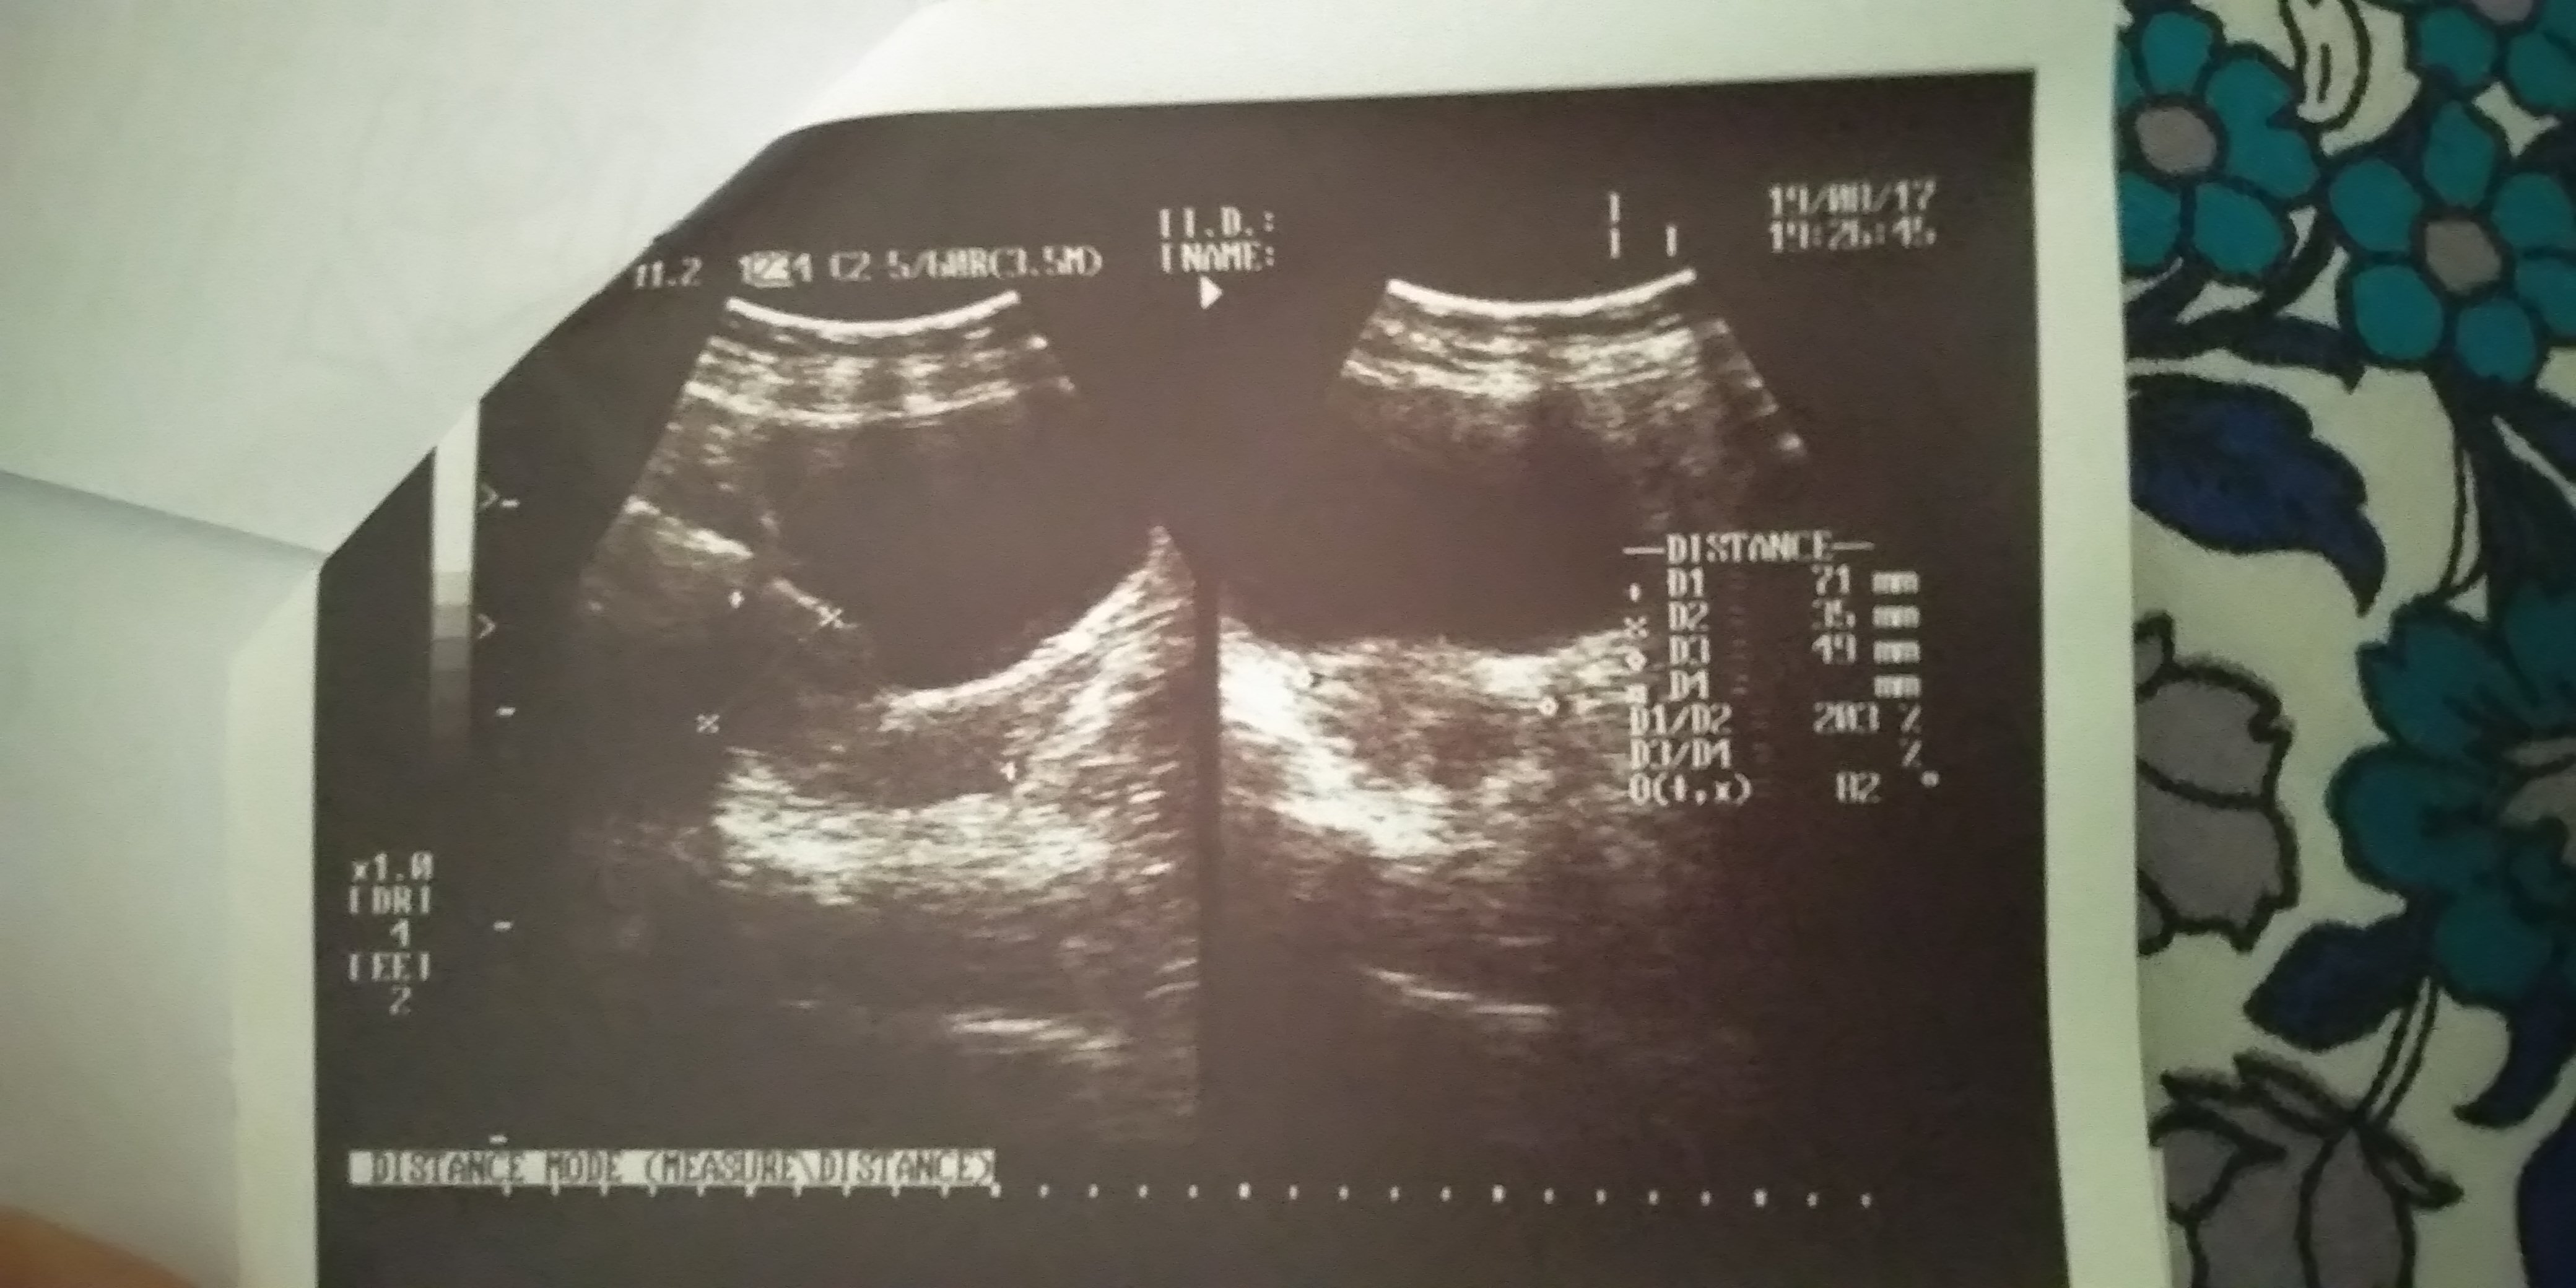

I have 28 days of cycle. it was 6 days over so i did a scan. Now after 7th day I started bleeding . want to ask if I conceived n miscarried or its just my normal periods? I have noticed relatively big lumps of blood on my pad.